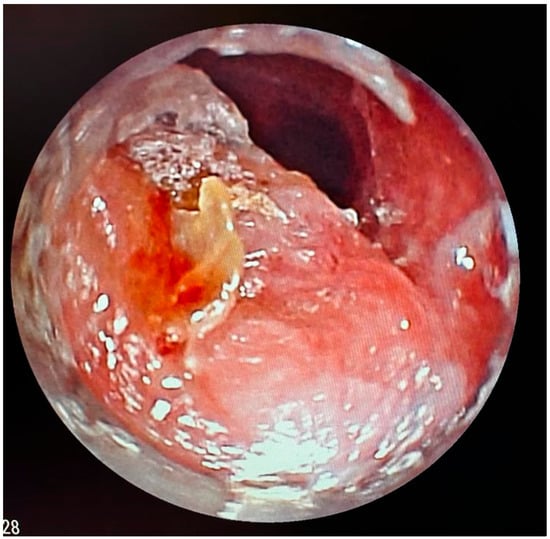

A flexible bronchoscopic examination under general anesthesia demonstrated extensive ulcerative granulation tissue distal to the tracheostomy cannula obstructing 60% of the tracheal lumen (Figure 1). To address this finding, the tracheal cannula was replaced with a longer cannula extending beyond the granuloma. The insertion of the extended cannula was performed under bronchoscopic guidance. A subsequent follow-up evaluation at six months revealed a substantial reduction in the granuloma’s size.

Figure 1. Tracheoscopic visualization of an obstructing granuloma at the distal end of the tracheostomy cannula.